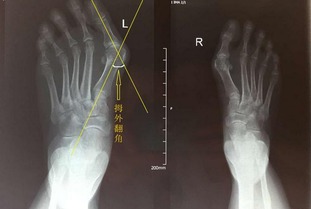

有些患者前足掌面可出现胼胝疼痛,值得注意的是畸形与疼痛不成正比,有的畸形很明显,但痛感并不十分明显。 拇趾外翻引起的胼胝体(脚垫、老茧子、鸡眼) 问:患者如何确定自己是否患有拇外翻呢? 答:拇趾外翻通常由患者自己发现,如果拇趾倾斜超过一定角度,且合并有拇囊炎疼痛(穿鞋磨鞋帮),一般即可诊断为拇外翻。

再者,X线也是重要的诊断依据。但是,怀疑诊断后最好请专科医师诊断。